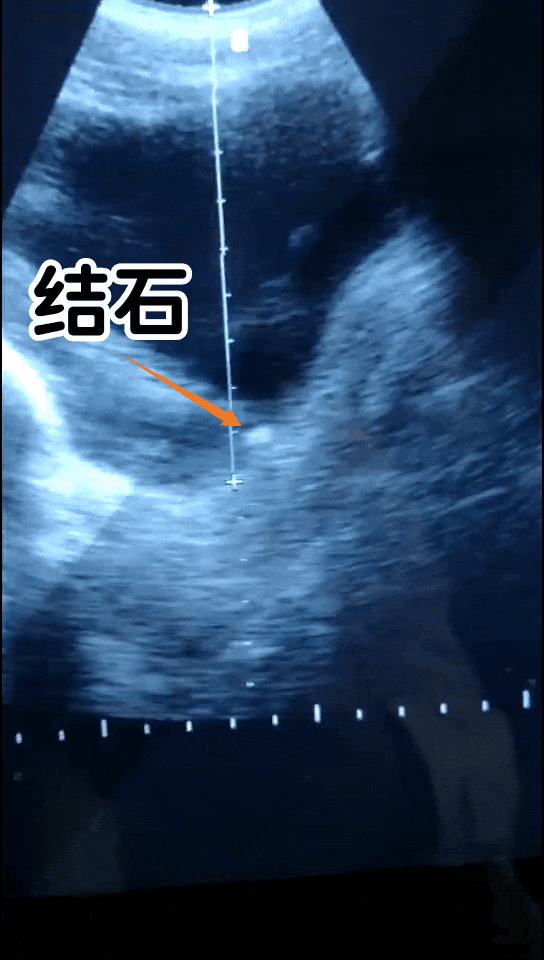

(碎石的瞬间)

结石经常反复发作的人群,建议定期做一次泌尿系统的B超检查,通过B超检查能早期发现结石可能。